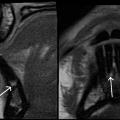

Update zu bildgebenden Verfahren in der Zahnmedizin: Aufnahmen zu Magnetom Free.Max dental edition (ddMRI)